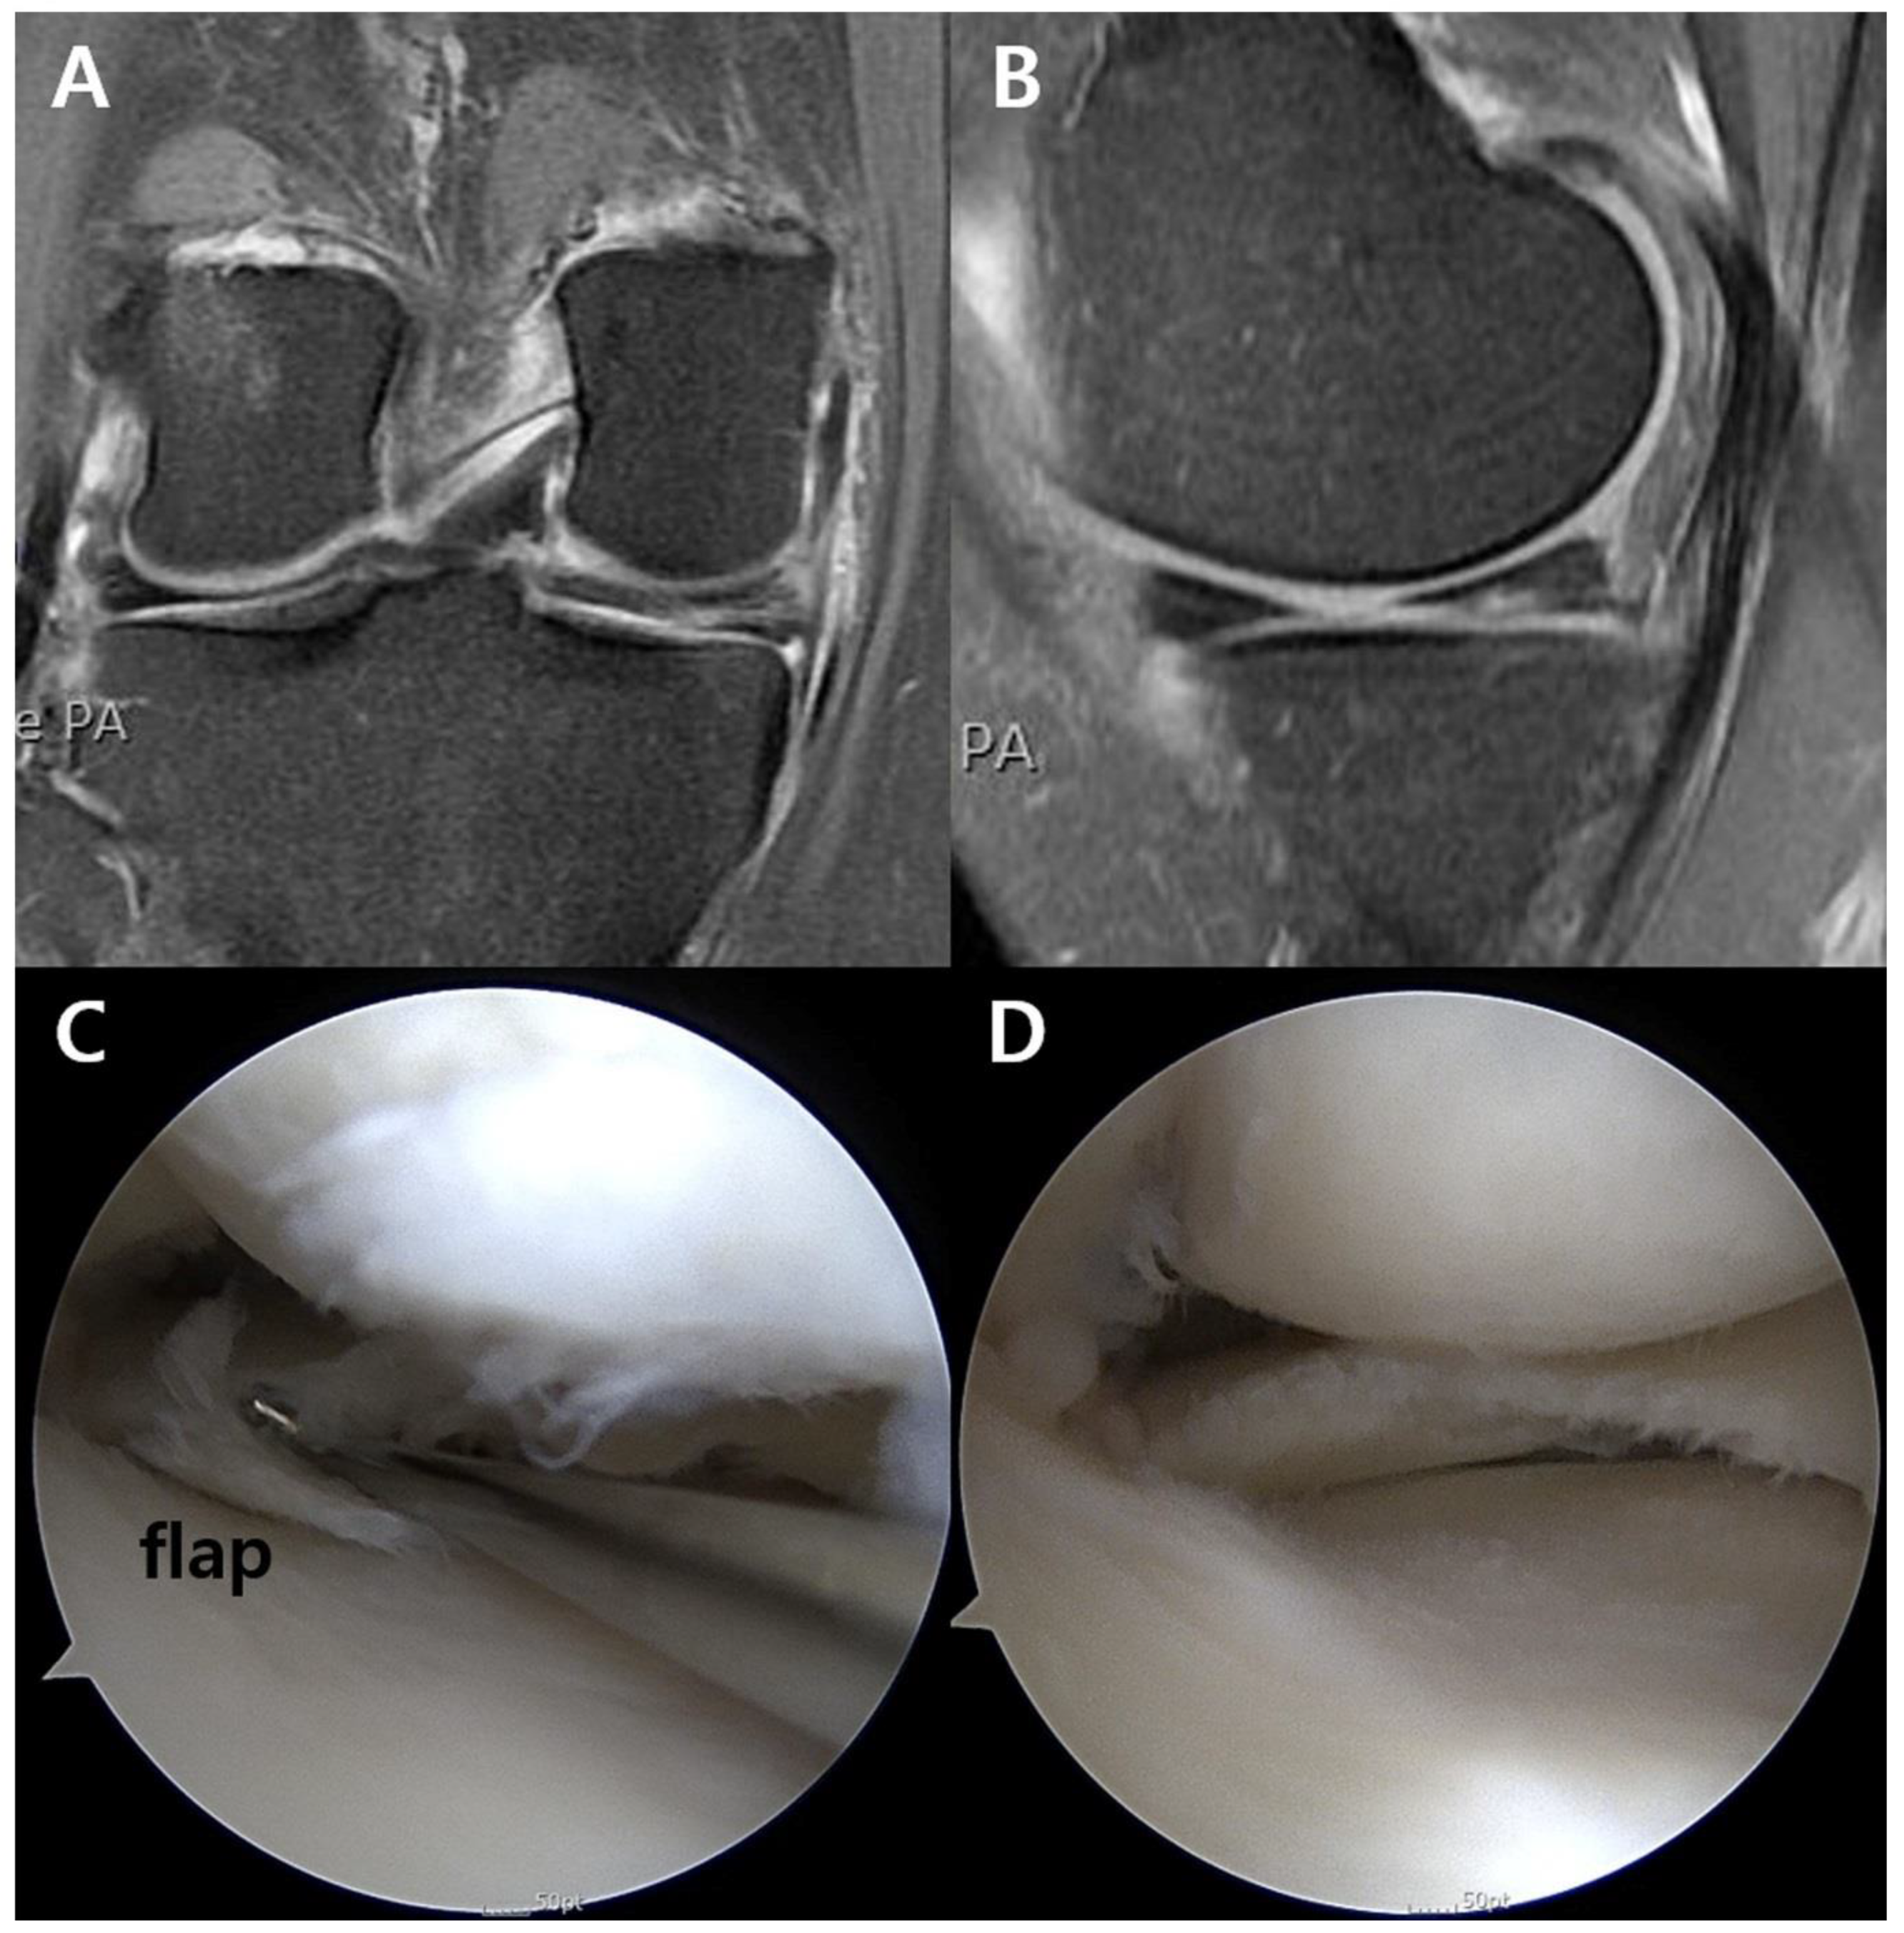

Figure 1.

Unstable flap at the posterior horn of the medial meniscus in the right knee. (A) Coronal and (B) sagittal MRI images did not definitely show the flap, which was (C) confirmed and (D) debrided during arthroscopy. MRI, magnetic resonance imaging.